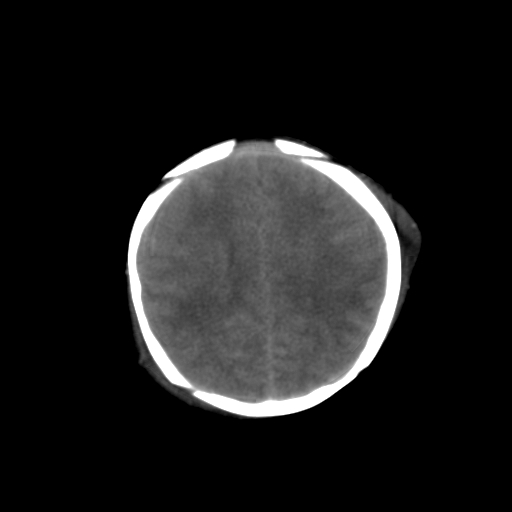

男,3天,患儿为剖腹产,生后嗜睡、拒乳。

1)考虑hie。2)sah?。3)右侧颞顶枕部及左侧颞顶部头皮血肿。

1、右侧颞顶枕部及左侧颞顶部头皮血肿。2、第五第六脑室。3、新生儿,脑白质密度还算可以,也无蛛血,不考虑hie。

脑室系统及脑沟裂闭塞,弥漫性脑密度减低,支持考虑hie,建议复查。右侧颞顶枕部及左侧颞顶部头皮血肿,另不除外胼胝体发育不良,复查